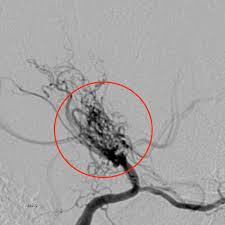

모야모야병은 뇌 기저부에 있는 주요 혈관이 점차 좁아지면서 뇌로 가는 혈류량이 줄어드는 질환입니다. 혈류가 부족해지면 뇌는 새로 가늘고 약한 혈관을 만들어 혈류를 보완하려고 하는데, 이 혈관들이 모여 있는 모습이 연기처럼 보여 ‘모야모야’라는 이름이 붙었습니다.